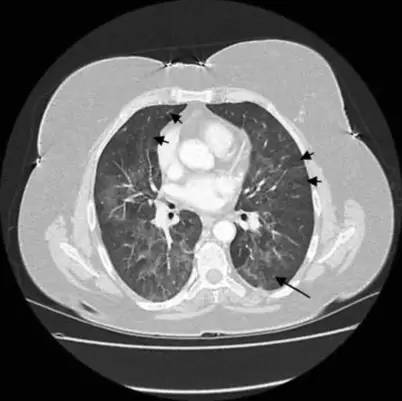

2013-11-20复查胸部CT提示双肺斑片影较前吸收(图1-图2),于2013-12-05出院,出院后服用醋酸泼尼松片 8mg 1次/日。患者仍喘息明显,日常生活不能自理。

图 1:2013年11月胸部CT

注:双肺弥漫性磨玻璃影及斑片影、可见空气潴留征及小结节影

图 2:2013年11月胸部CT